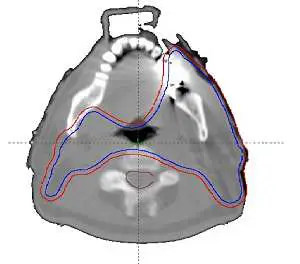

圖片為頭頸部(head and neck)軸位(axial)CT 影像,可見兩條等劑量線(isodose line)輪廓:

- 紅色輪廓:外側較大的靶區邊界,呈現凹形(concave)包覆,兩側延伸包括頸部淋巴引流區

- 藍色輪廓:較外側的等劑量覆蓋線,貼合凹形靶區外緣

影像中可見靶區中央(兩側靶區的凹入處)對應脊髓或其他危急器官,即形成 concave shape 靶區結構——靶區在中間因危急器官存在而「凹入」(如馬蹄形)。

此類 concave PTV 是 IMRT 最典型的適應症:靶區圍繞著危急器官(如脊髓、腦幹),一般的方形野或簡單 3D 順形技術無法在保護危急器官的同時維持靶區劑量均勻覆蓋。